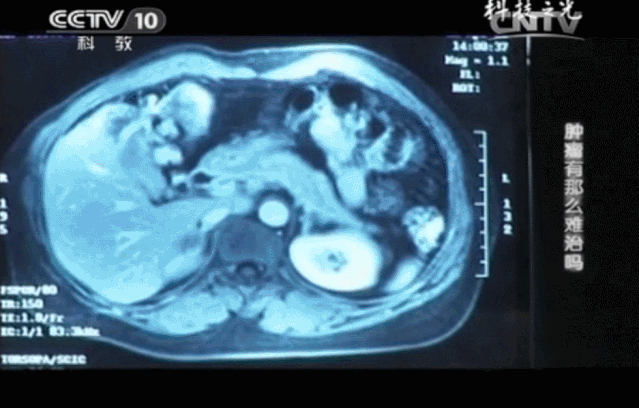

化疗虽然能杀伤癌细胞,可副作用也极其大,三个月过后,身体的缺陷再加上忍受疾病的心理压力,王女士已被折磨得不成人形。没过多久,噩耗再次传来,王女士的肝脏上毫无征兆地出现了一个直径约为8cm的肝转移肿瘤,继续化疗只会加重她的身体负担,遏制肿瘤的效果也并不尽如人意。

不仅如此,连续4个月的CT结果对比分析,肝转移瘤从8公分缩小到2.5公分,肿瘤标记物指标回归正常,这些都说明肿瘤正在被免疫细胞一点点消灭。王女士终于回归了正常的生活。